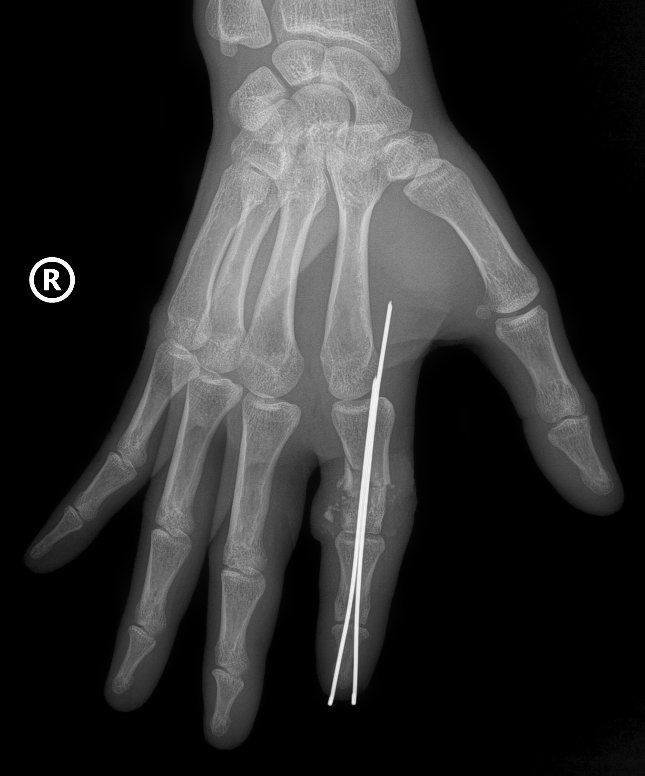

Hình ảnh X-quang phần ngón trỏ tay phải bị đứt rời của thủy thủ 38 tuổi được định vị và cố định bằng kim chuyên dụng

Hai kíp phẫu thuật được triển khai song song, một kíp làm sạch và chuẩn bị phần ngón đứt rời, kíp còn lại chuẩn bị phần mỏm cụt. Xương ngón được định vị và cố định bằng kim chuyên dụng để tạo trục vững, hệ thống gân và dây chằng được phục hồi.